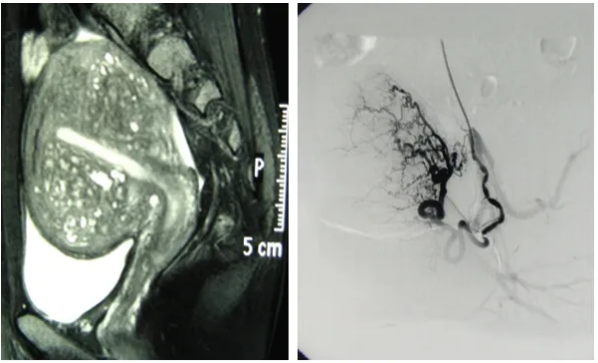

2. 精准导航:在数字减影血管造影(DSA)设备的实时引导下,将一根纤细柔软的导管,经血管系统精准送达子宫的供血动脉。

3. 靶向栓塞:通过导管,将大小适宜的栓塞颗粒注入目标血管。这个过程是可控且可视的。

在洛阳白马医院介入科,我们致力于为患者提供专业的微创介入诊疗服务。科室配备了可用于血管介入治疗的数字减影血管造影(DSA)系统,为治疗的精准实施提供了设备支持。

科室的独建库医生,在介入诊疗领域拥有多年的工作经验。独医生在子宫腺肌症、子宫肌瘤等疾病的介入治疗方面积累了一定的临床认识,能够根据患者的具体情况,参与评估介入治疗是否为其合适的选项之一。

我们的工作重点,在于通过详细的术前评估、精细的术中操作和全面的术后随访建议,为患者提供一种专业、微创的治疗选择。